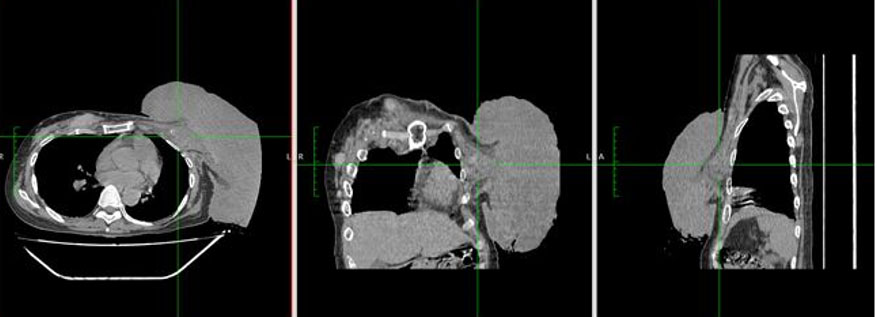

On chest computed tomography (CT) scan, the mas is intimately related posteriorly and cannot be separated from the thickened left pectoralis major muscle. There is a subcentimeter, non-calcified pulmonary nodule in the perifissural region of the anterior segment of the right lower lobe (Figure 4). No liver lesions noted on abdominal CT.

Figure 4: Chest CT scan. Noted a fungating, lobulated, heterogeneously enhancing left breast mass, ~23.1 × 18.9 × 17.5 cm. No normal looking left breast. Mass is intimately related posteriorly, and cannot be separated from the thickened left pectoralis major muscle, likely involved.